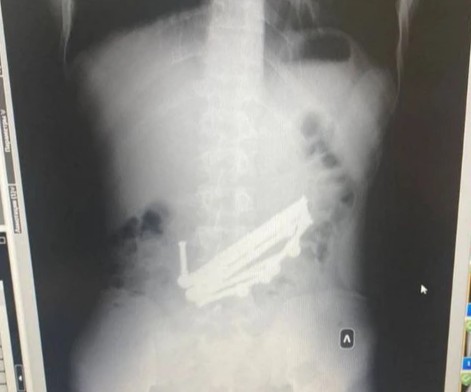

Сделав рентген, медики были шокированы количеством инородных предметов в его желудке и пищеварительном тракте. Оказалось, что молодой человек решил попробовать на вкус детали магнитного конструктора и проглотил детали, общим весом 420 граммов. По данным Минздрава региона, после юноша две недели ходил с инородными предметами, надеясь, что они сами выйдут из организма. Но затем у него разболелся живот, и он обо всем рассказал родителям.

В больнице парню провели срочную двухчасовую операцию и извлекли магнитные детали. Сейчас пациент идет на поправку.